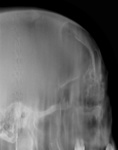

Фрагменты рентгенограмм.

Признаки прерывания кортикального слоя?